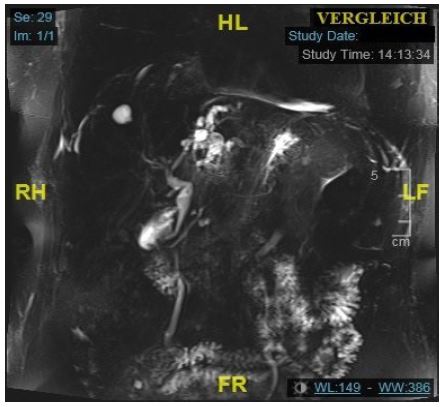

Over the following years, the patient remained asymptomatic, with regular ultrasounds showing no progression of the left biliary duct dilatation. After six years, the patient was hospitalized with acute cholecystitis due to cholelithiasis. An abdominal Computer Tomography (CT) scan revealed a gallbladder wall thickening with a stone in the infundibulum and the known left bile duct dilatation. The serum CA 19-9 was elevated at 640.4 U/ml (reference: < 37 U/ml). A conservative management of the cholecystitis with antibiotics was employed and the patient was subsequently discharged without any symptoms. Two months later, the patient was readmitted with cholangiosepsis by Escherichia coli. CT and Magnetic Resonance Cholangiopancreatography (MRCP) showed no progression of the left bile duct stricture and dilatation (Figure 2). MRCP presented an echo-rich formation around the left hilum (sludge), suggesting cholangitis, but no signs of choledocholithiasis or alterations in the liver parenchyma. An ultrasound examination of the abdomen confirmed those findings. The patient underwent an early elective cholecystectomy. The gallbladder histology showed no malignancy. At this timepoint, a diagnosis of cholangiocellular carcinoma was deemed unlikely due to the absence of lymphadenopathy and consistent clinical and radiological findings.

Figure 2: Coronar T2w MRCP: Known dilatation of the left bile duct during first episode of cholangitis.